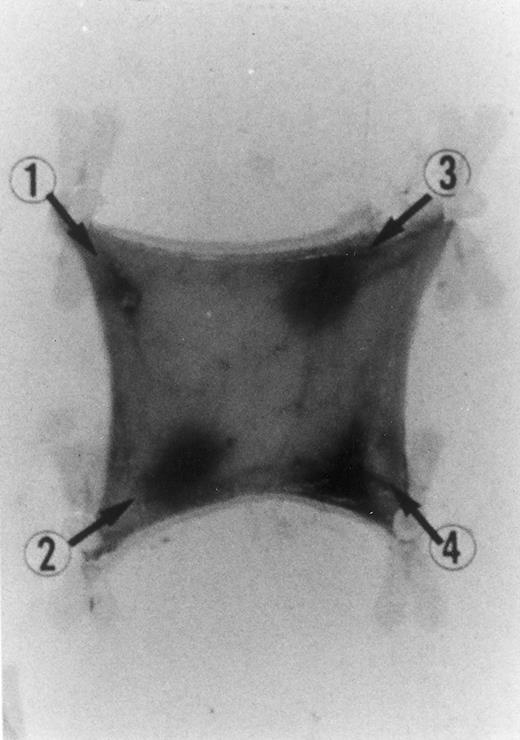

Electron microscopy of skin injection sites.To better analyze the skin injection sites exposed to RANTES, an electron microscopic study was performed. Here we show a representative experiment of four (Fig 4). This electron micrograph (×13,800) depicts accumulation of four basophilic cells (a), one eosinophil (b), and a macrophage (c), 4 hours from injection, with a pattern describing a typical inflammatory event and showing chemoattraction activities toward several cell types.

Transmission electromicrography of a representative experiment of rat inflamed injection site produced by RANTES 10 ng. The section showing the kinetics of the dermal response to exogenous RANTES 4 hours after injection. Evidence for intravascular activation of basophilic cells (a), eosinophil (b), and macrophage (c). Original magnification × 13,800.